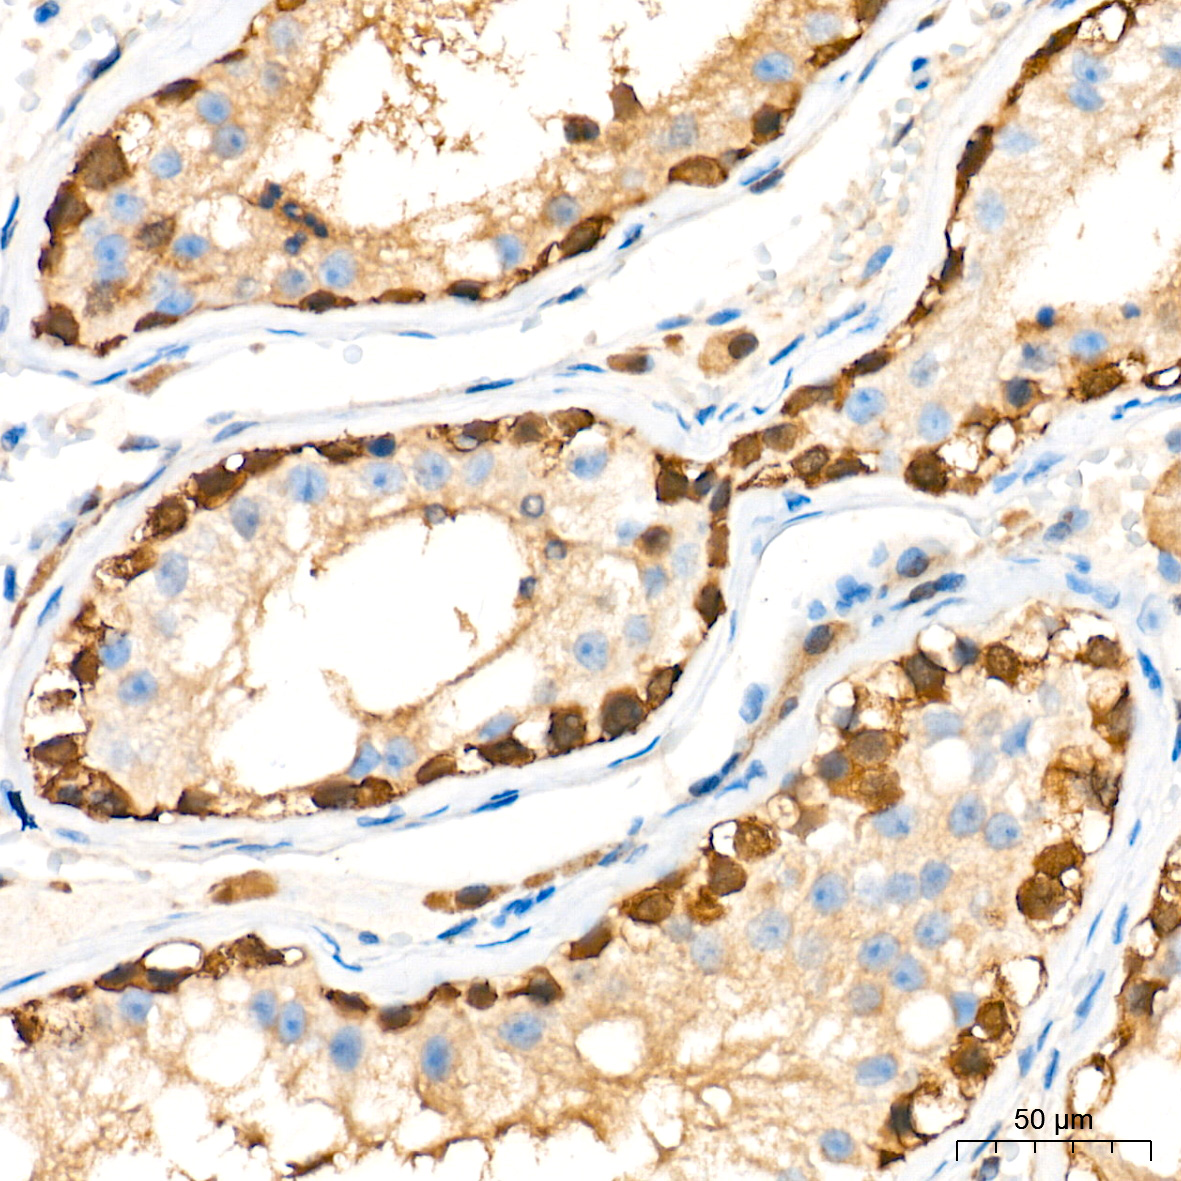

ABclonal基于第四代重组兔单抗SMab®技术平台,以ISO9001和ISO13485质量管理体系标准,为科研工作者研发并生产了一系列高特异性和高稳定性重组单克隆和多克隆抗体产品,这些抗体已针对多种应用进行了全面验证,用于神经谱系、神经退行性疾病(阿尔兹海默症、帕金森氏症、神经炎症)、神经发生、神经营养等神经生物学研究!

中枢神经系统由神经元和胶质细胞组成,神经元主要功能是传递信息,胶质细胞可为神经元提供物理和营养支持。在神经系统发育过程中,神经干细胞(NSC)能够分化为多种神经系,包括神经祖细胞、各类神经元细胞、星形胶质细胞和少突胶质细胞。小胶质细胞在发育过程中迁移到中枢神经系统,参与正常神经系统功能的建立,以及炎症反应。神经谱系标志物可对不同神经细胞类型进行标记和研究,获取关于其形态特征和特定蛋白质表达的信息,从而了解神经系统的分子、细胞和功能过程及其在发育、衰老和疾病中的作用。